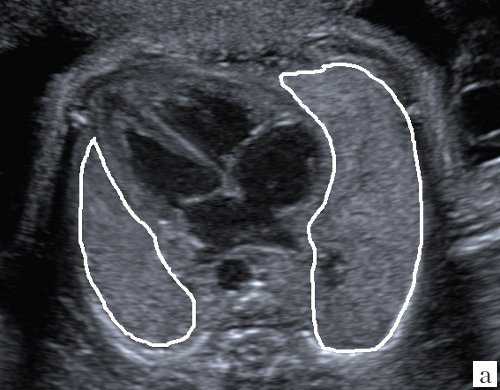

Для уменьшения расхождения в оценке ЛГО в норме и при диафрагмальной грыже группой авторов под руководством С. Peralta и K. Nikolaides [2] произведено сравнение возможных методов измерения легких. Было доказано, что метод трассировки (длина контура) дает наименьшие расхождения в измерениях между специалистами; метод двух перпендикуляров (перемножение максимальных диаметров) является наиболее популярным, но в неопытных руках может существенно (до 45%) завышать размеры легкого, метод с включением в расчет переднезаднего размера легкого наименее воспроизводим, поскольку нет точных ориентиров установки калиперов переднезаднего размера (рис. 3).

а) Метод трассировки.

б) Метод двух перпендикуляров (метод максимальных диаметров).

в) Метод оценки переднезаднего размера.